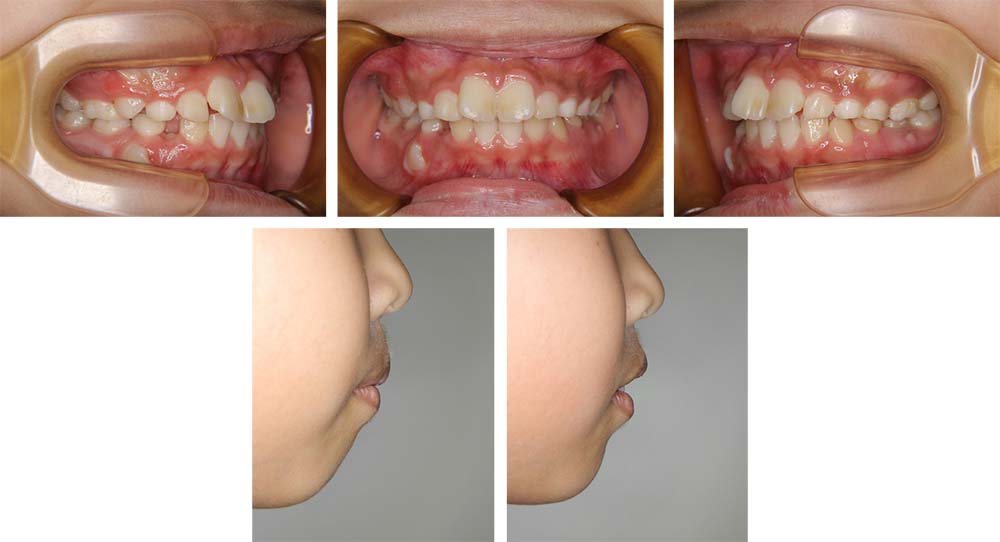

初診時

治療前

治療後

上顎前歯のねじれと前歯の前突を主訴に来院された。口元の突出があり、セファログラムの分析を基に前歯部叢生を伴う上下顎前突と診断し、上下顎前歯を整え後退を行うことを治療目標とした。側方歯の交換期に入っていたことから、永久歯への生え代わりを待ち、13歳まで経過観察を行った。永久歯への生え代わりが終了し、下顎第二大臼歯の萌出を認めたことから、上下顎小臼歯を抜歯していただき前歯を後退させるために上下顎唇側マルチブラケット装置を使用して動的治療を行った。矯正用ゴムの使用やブラッシングなど協力状態も極めて良く、前歯が適正な状態に後退して、上口唇がE-ラインから2㎜程度、下口唇はE-ライン上にそれぞれ後退し、美しいオトガイ形態となって口元の安寧を得ることができた。臼歯部の咬合状態も良好な状態であった。動的治療期間2年2か月間。